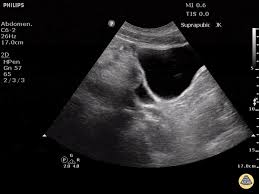

THE READ ON THIS FINDING.

WHAT IS POSITIVE FAST EXAM?